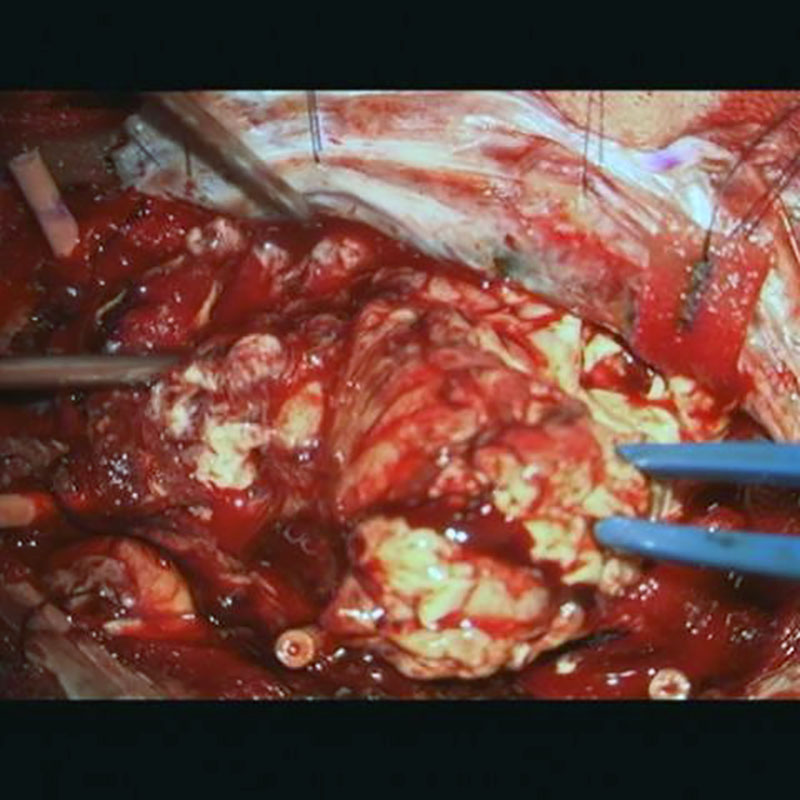

術中写真

摘出 前

摘出 中

摘出 後